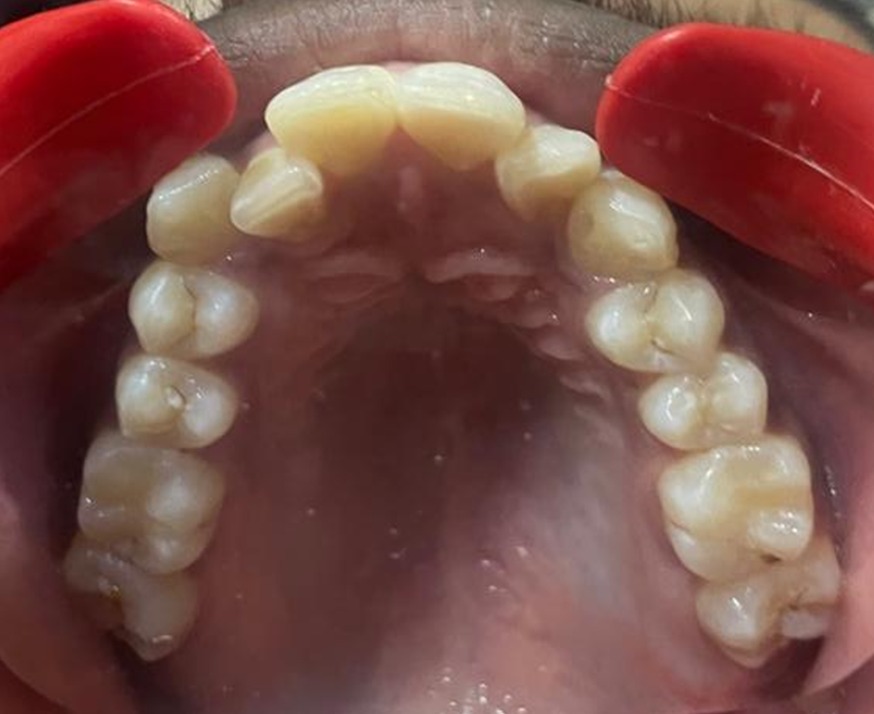

Before & After Results

At Aline Dent, we take pride in delivering visible and lasting improvements in our patients’ smiles. Our before-and-after results highlight the effectiveness of modern dental treatments combined with personalized care. This gallery showcases real dental cases treated at our clinic, giving you a clear idea of how different dental concerns can be corrected with the right treatment approach.

From minor corrections to complete smile enhancements, these teeth transformation results demonstrate how professional dental care can improve both oral health and appearance. Our experienced dental team carefully evaluates each patient’s needs and creates customized treatment plans to achieve natural, healthy, and confident smiles.

In this gallery, you will find a variety of smile makeover cases, including treatments for crooked teeth, gaps, discoloration, damaged teeth, and other common dental concerns.